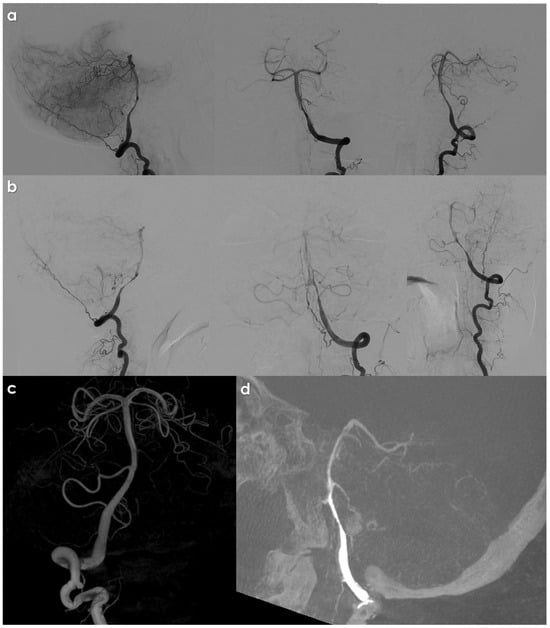

Figure 2 illustrates an example of an intracranial VAD on DSA.

Figure 2.

DSA from left (panels (a,b,d)); left (panel (c)) VA injection in a patient with left intracranial VAD, showing a long, irregular, tapered stenosis of the left V4 VA, immediately after PICA take off. Panel (c) shows the right VA reconstructed in volume rendering from a 3D rotational angiography acquisition. In panel (d), the source images of the 3D RA are reconstructed in an MIP/MPR protocol in a sagittal oblique plane passing though the left V4 VA.